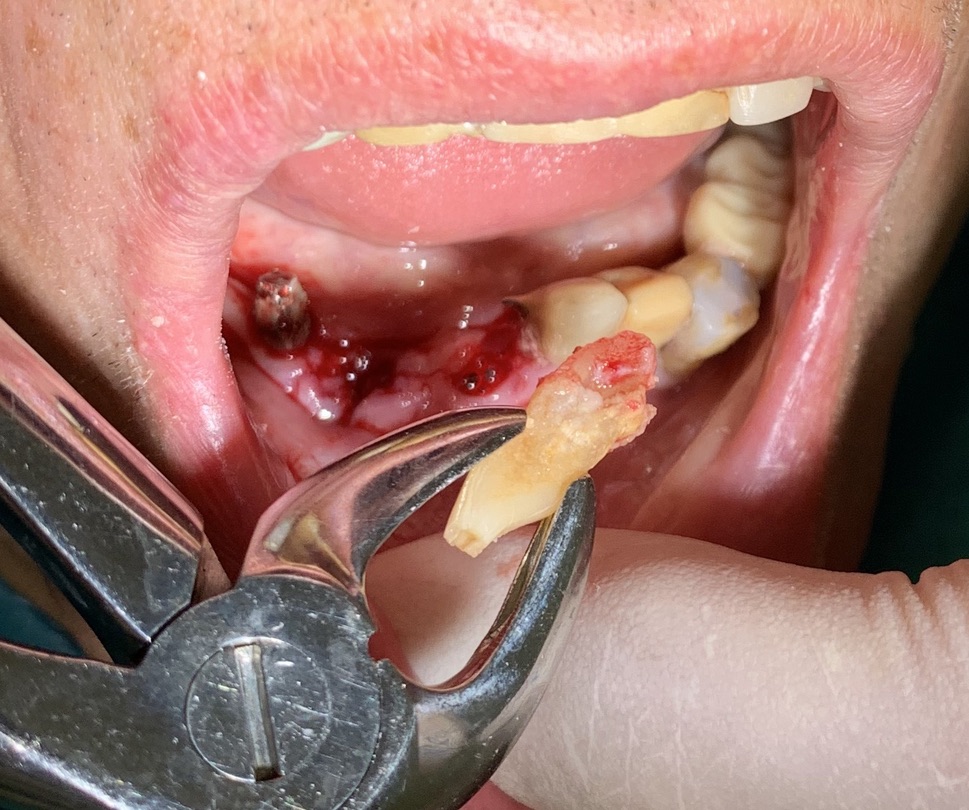

Extractive situation: immediate post-extraction implants

As shown in the extract from the chronological registry of implants shown above, the patient underwent several times to implant operations, facing sectoral problems as they arose.

This time the patient wanted to undergo the operation under general anesthesia, carried out at our clinic in Acquafredda with a well-equipped anesthetist with long experience.

The second aspect strictly dependent on the patient's implant history was the presence of corrected disparallelisms at the end of the surgery before providing him him with a temporary phosesiscircular. At the end of the session at 11.45. all implants appear solid and without signs of evident peri-implantitis or mucosal inflammation.